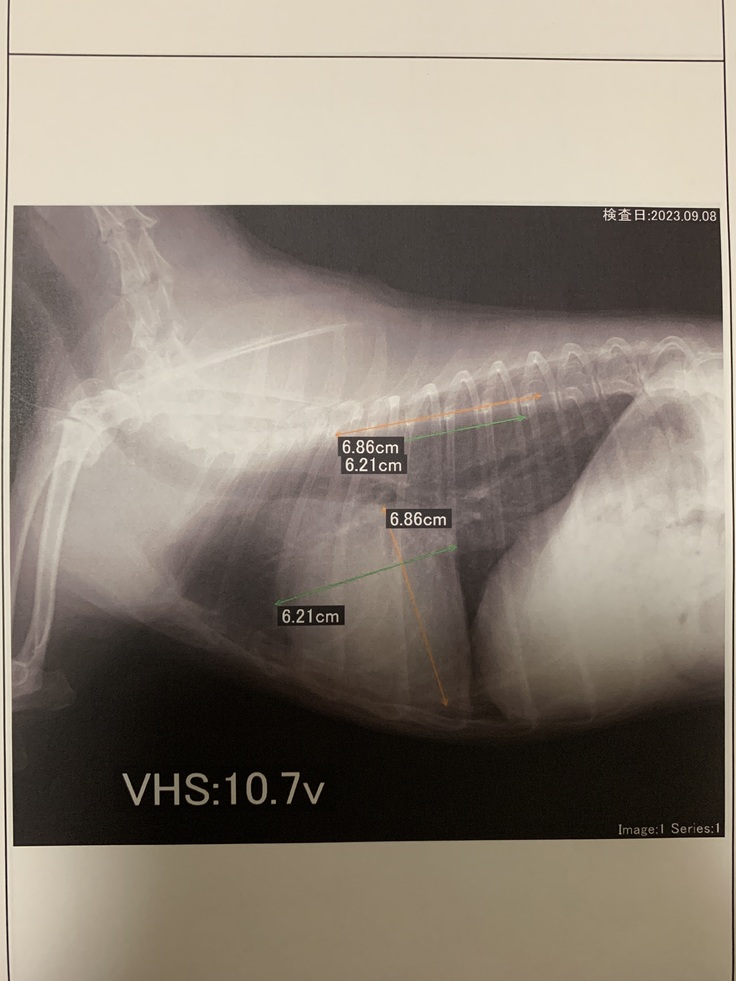

※レントゲン写真

レントゲン写真では、心臓が肥大しており、クラスb2の(心不全発症)直前レベルである事も分かりました。 心臓から送りだす血液には逆流が見られ

重度のレベルであり、

やはり手術しないと治らないと判断されました。